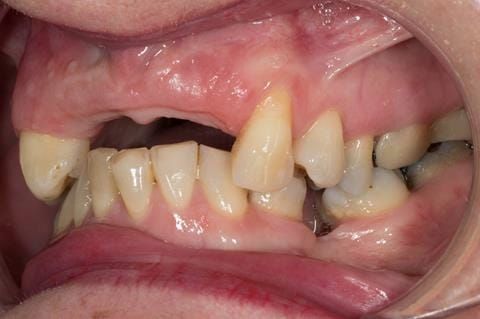

- UR2 peri-radicular periodontitis with a peri-radicular area on the root apex. Retrograde amalgam filling from a previous apicectomy. No visible root canal or root canal filling. Large circumferential marginal gap between the crown and tooth. Large post and core present. Very little tooth structure remaining resulting in a fragile tooth with increased potential for fracture.

- UR1 peri-radicular periodontitis with a small peri-radicular area on the root apex with wide blunderbuss apex. Radio-opaque root canal filling present approximately 3 mm short of the radiographic apex. Large circumferential marginal gap between the crown and tooth. Large post and core present. Very little tooth structure remaining resulting in a fragile tooth with increased potential for fracture.

- UL1 peri-radicular periodontitis with a peri-radicular area on the root apex. Retrograde amalgam filling from a previous apicectomy. Visible root canal space with no sign of root canal filling. Large circumferential marginal gap between the crown and tooth. Large post and core present. Very little tooth structure remaining resulting in a fragile tooth with increased potential for fracture.

- UL2 peri-radicular periodontitis with a peri-radicular area on the root apex. No visible root canal or root canal filling. Large circumferential marginal gap between the crown and tooth. Large post and core present. Very little tooth structure remaining resulting in a fragile tooth with increased potential for fracture.

- High smile line showing gum above gingival zeniths of upper front teeth when smiling. Aesthetic failure of the upper four incisors with inflammation of the gingivae and mis-match of the gingival zenith levels.

- Other than the maxillary incisors the remaining dentition was in marginally better condition being moderately to heavily restored. Many will probably require replacement and restoration from time to time mainly from wear and tear owing to occlusal forces.